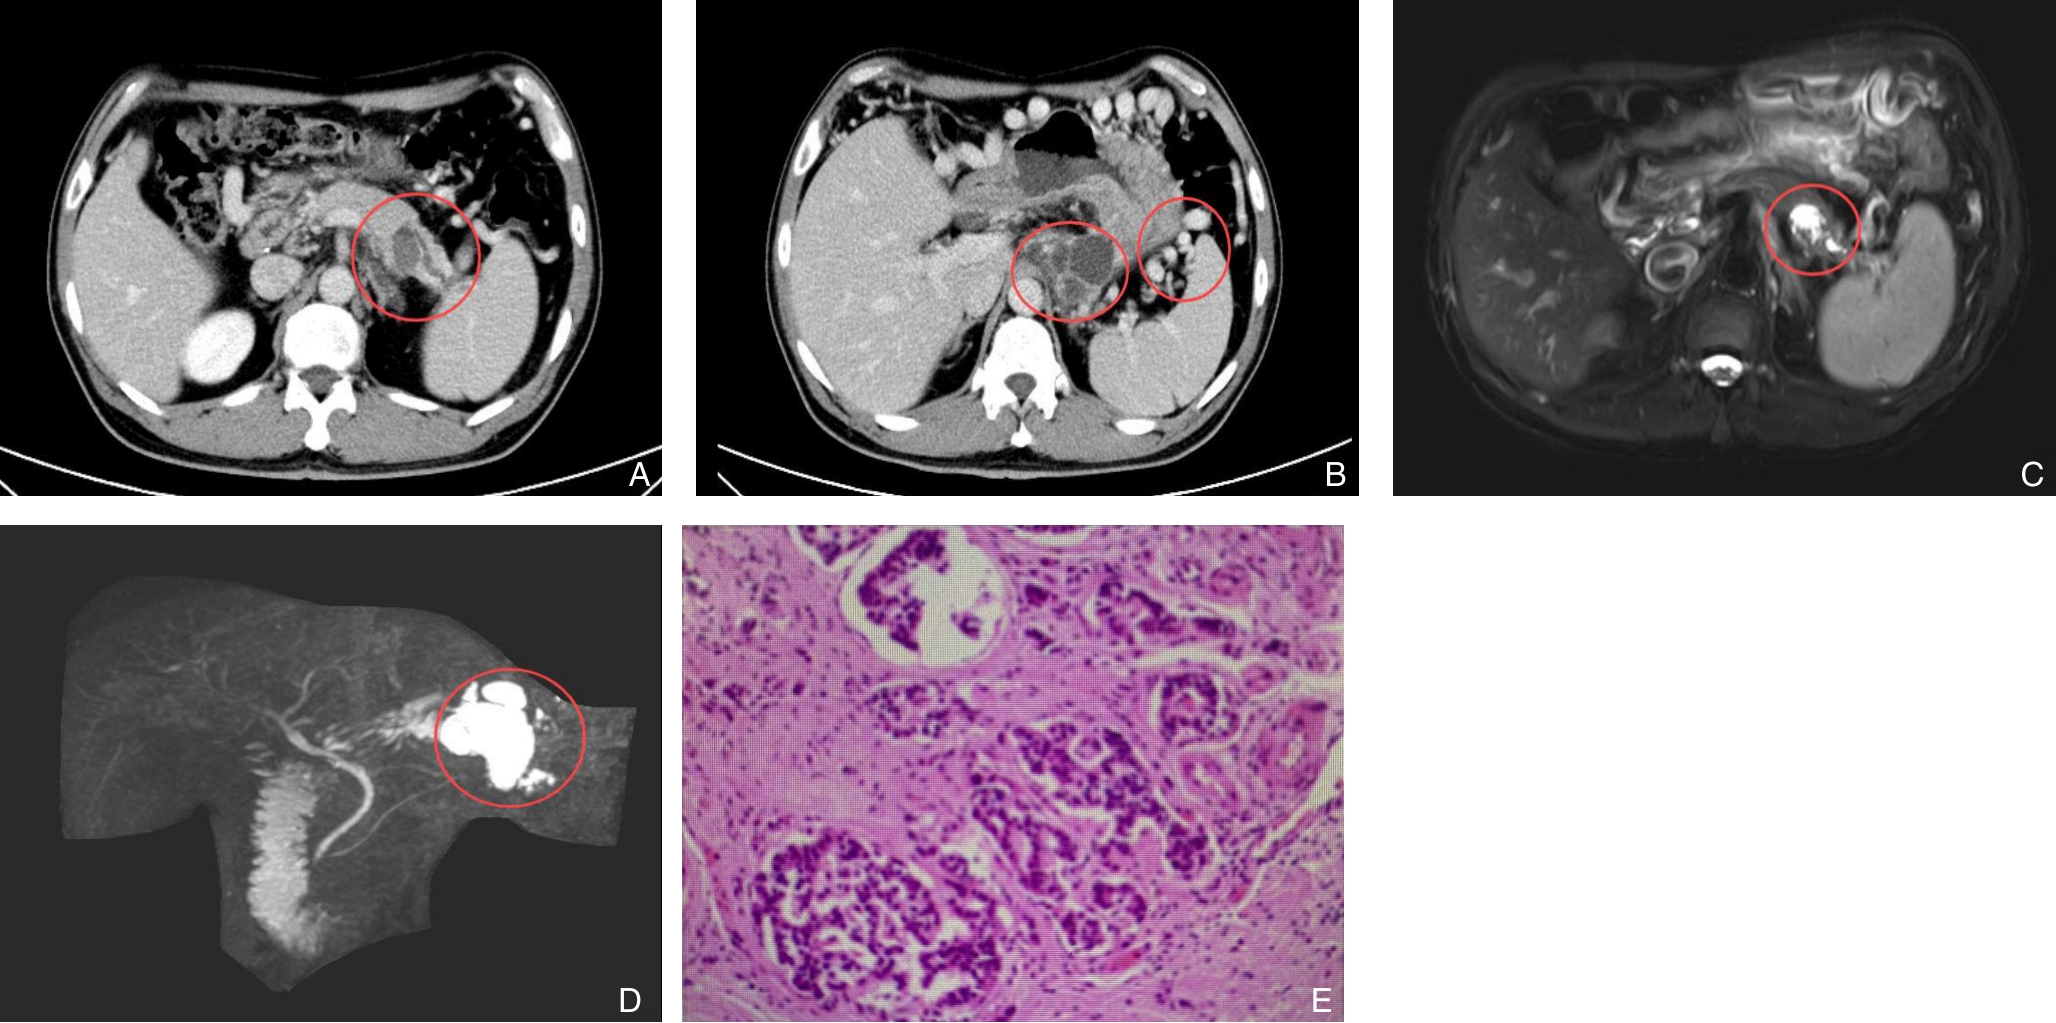

摘要:背景与目的 复发性急性胰腺炎(RAP)病因复杂,其中由寄生虫感染引起者极为罕见。胰腺阔盘吸虫侵入胰管导致梗阻并诱发RAP,目前国内尚无报道。本研究通过1例确诊病例,结合文献复习,探讨其临床特征、诊断难点及防治要点。方法 回顾分析湖南师范大学附属第一医院2023年收治的1例胰腺阔盘吸虫致RAP患者的临床资料,包括影像学、手术及病理学结果,并综述国内外相关文献。结果 患者为59岁女性,表现为反复上腹痛4年。影像学提示胰体尾部多囊性病变并胰管扩张,术前被考虑为胰管内乳头状黏液性肿瘤。行腹腔镜胰体尾及脾切除术后,病理证实导管内存在吸虫虫体及虫卵,最终确诊为胰腺阔盘吸虫感染。术后恢复良好,随访1年未再发胰腺炎。结论 胰腺阔盘吸虫是RAP罕见的病因,临床及影像学表现缺乏特异性,易误诊为胰腺囊性肿瘤。对于病因不明的RAP,尤其是有食用生食或野味史的患者,应重视寄生虫学检查,如粪便虫卵及血清抗体检测,以早期确诊并指导治疗。